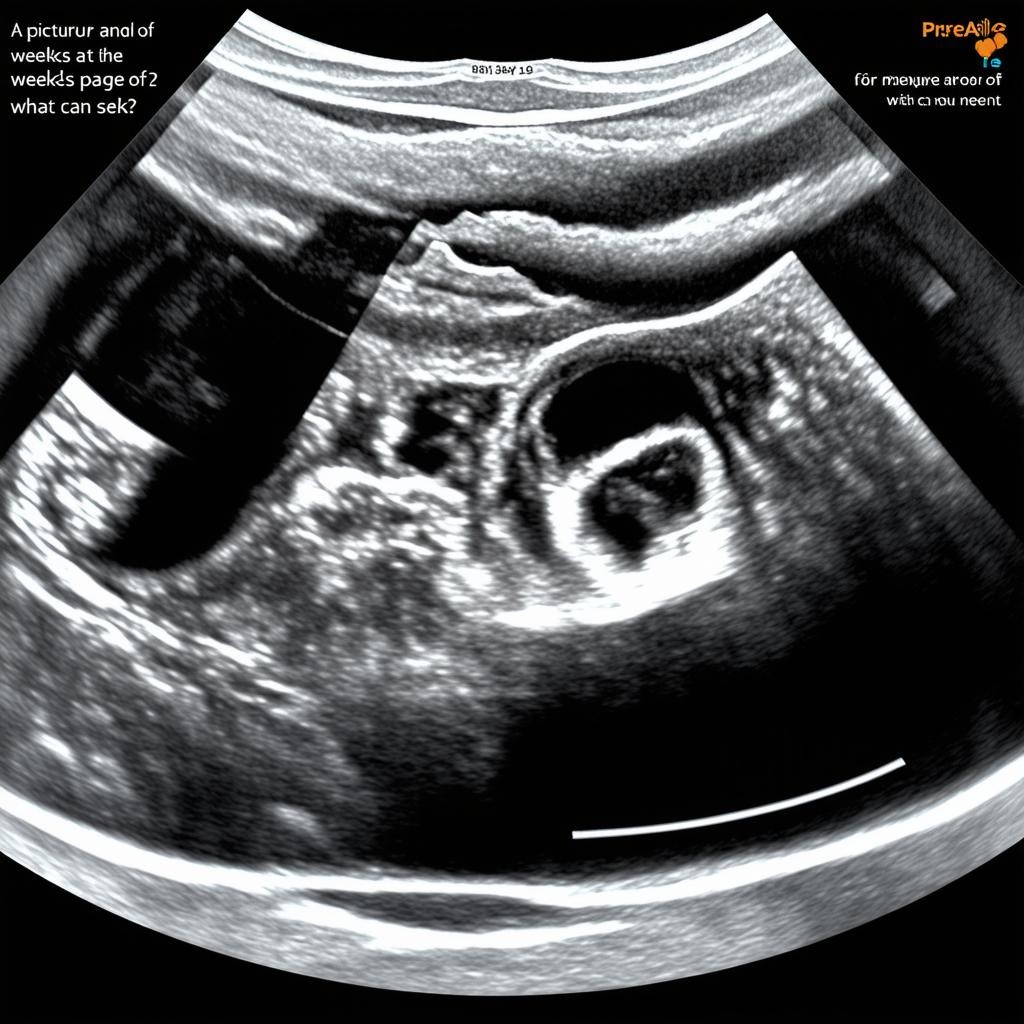

УЗИ на 12 неделе беременности: что показывает снимок?

Что видно на снимке УЗИ?

На УЗИ в 12 недель можно увидеть следующие структуры и параметры:

- КТР (копчико-теменной размер): Около 5-6 см, что соответствует сроку.

- Толщина воротникового пространства (ТВП): Норма — до 2,5 мм. Увеличение может указывать на риски хромосомных аномалий.

- Носовая кость: Должна быть видна, её отсутствие — тревожный признак.

- Сердцебиение: Норма — 140-170 ударов в минуту.

- Положение плода: Обычно свободное, так как места в матке ещё много.